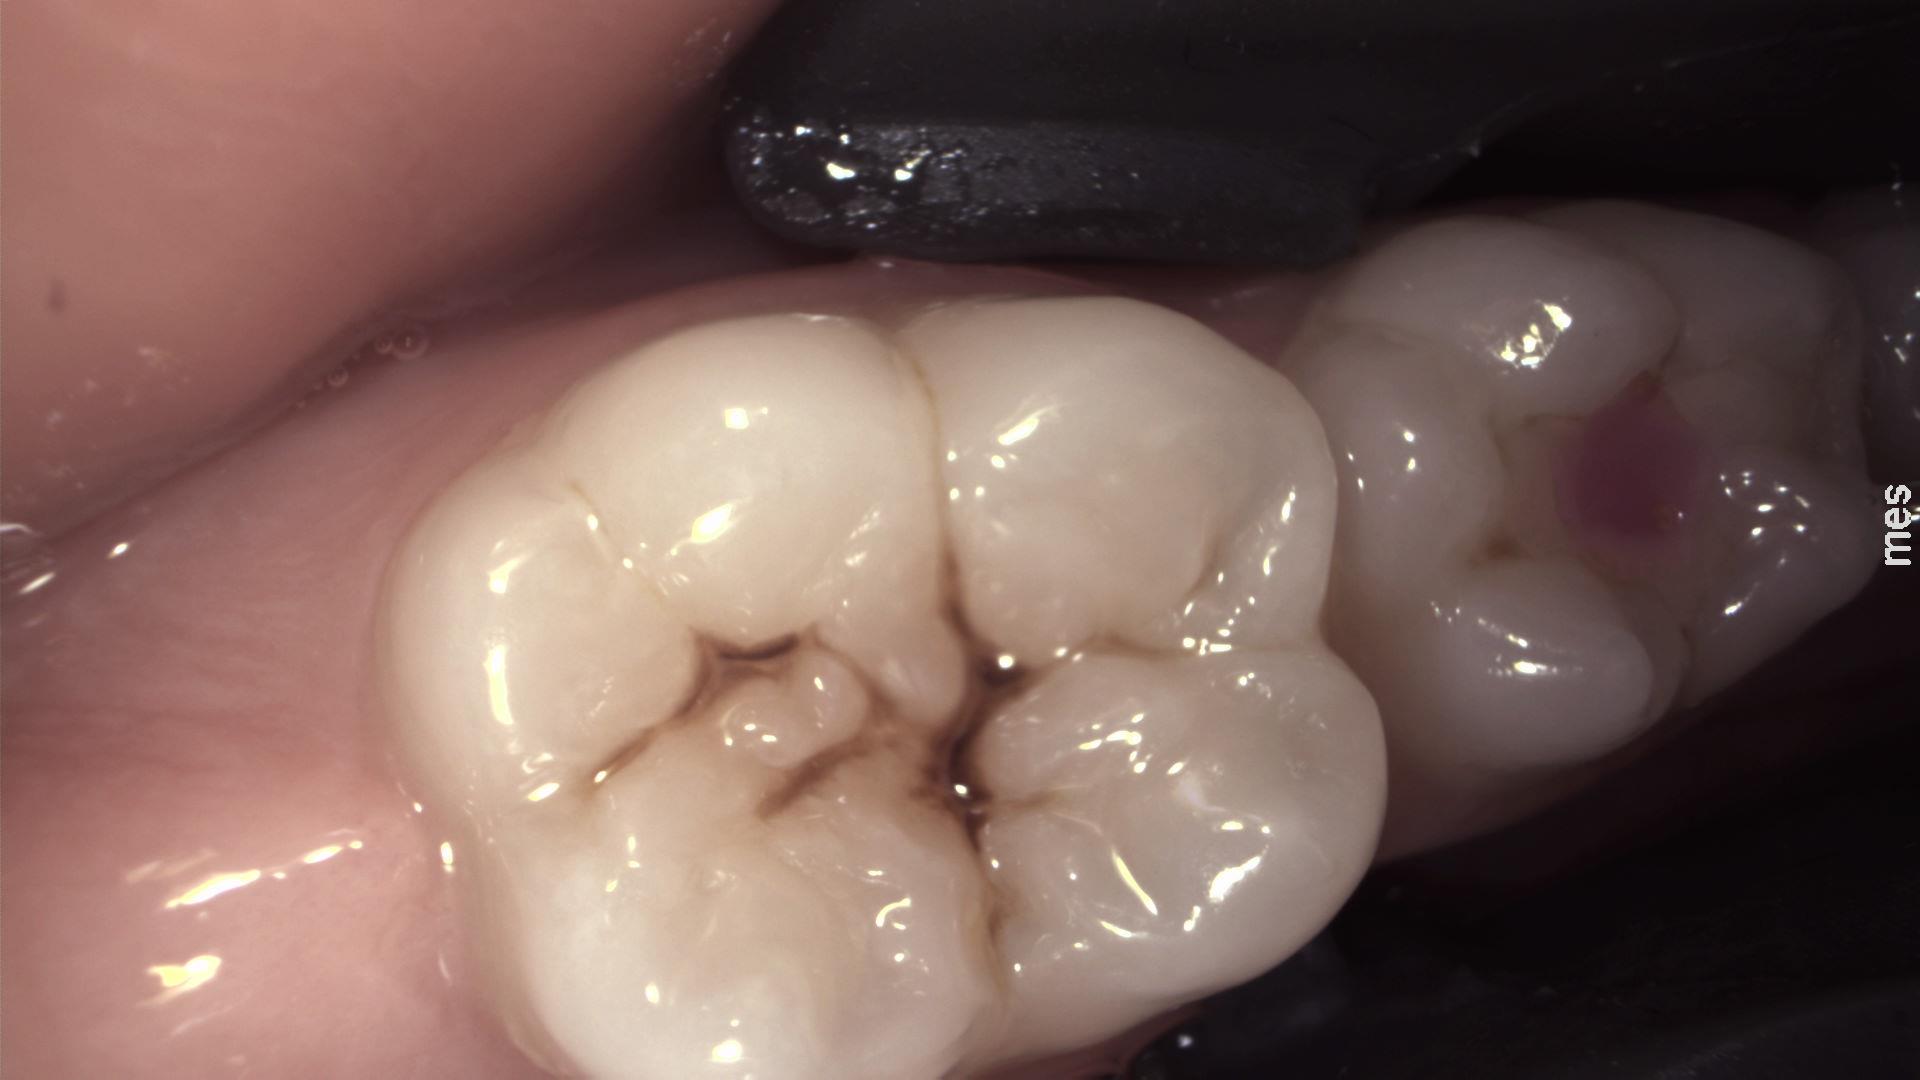

Takie potrojone obrazowanie pozwala na dokładną diagnostykę zmian próchnicowych, ewentualnej obecności płytki bakteryjnej na powierzchni zębów oraz prezentację wyników diagnostycznych pacjentom w sposób nie budzący żadnych wątpliwości. Cały proces badania realizowany jest tym samym urządzeniem, podłączonym do komputera i monitora. Lekarz dostaje do dyspozycji trzy obrazy: diagnostyczny z kamery IR (najbardziej mu potrzebny), rzeczywisty z kamery wewnątrzustnej (najbardziej trafiający do pacjenta), oraz fluorescencyjny (najbardziej motywujący do leczenia i poprawy higieny), a wszystkie obrazy mają dokładnie tą samą projekcję i łatwo je ze sobą porównać. Technologia NILT umożliwia wykonanie prześwietlenia zęba i zdiagnozowanie zmian próchnicowych o każdym stopniu zaawansowania.

Zdjęcie wykonane kamerą fluorescencyjną pozwala obrazować wypełnienia kompozytowe i złogi płytki nazębnej na powierzchni zębów, co może być przydatne przy motywacji małych pacjentów do lepszej higieny jamy ustnej.

Pierwsze z trzech wykonanych jednocześnie zdjęć stałego zęba trzonowego przy pomocy DIAGNOcam z wykorzystaniem kamery rejestrujące światło widzialne. Ten obraz jest najbardziej czytelny dla pacjenta.